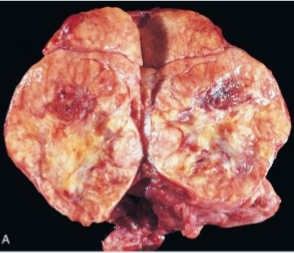

Thyroid Moderately enlarged thyroid

Rubbery, nodular fleshy cut surface

Chronic Lymphocytic Thyroiditis (Hashimoto Thyroiditis)

Infiltrate of Lymphocytes with germinal centers (Struma Lymphomatosa)